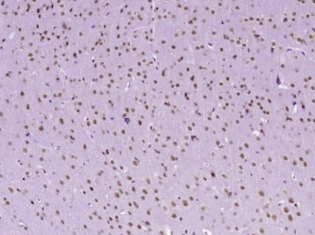

多聚甲醛固定,石蜡包埋(小鼠脑);用柠檬酸钠缓冲液(pH6.0)煮沸15min后获得抗原;用3%过氧化氢阻断内源性过氧化物酶20分钟;阻断缓冲液(正常山羊血清)在37℃下30min;用(磷酸-ATF2(Ser90))多克隆抗体进行抗体孵育。1:400在4°C下过夜,然后根据SP试剂盒(兔子)说明和DAB染色进行操作。